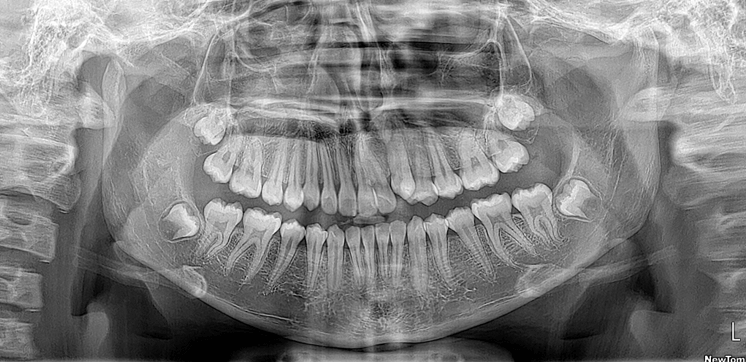

Para diagnóstico radiológico se utiliza CBCT bimaxilar FOV 10 x 8 realizada previo a la colocación de aparatología fija, en donde se observa al diente 1.1 retenido en el piso de fosas nasales en posición horizontal con su saco pericoronario desprovisto de recubrimiento óseo en el borde incisal. (Fig 5)

Fig 5. Cortes en ventana MPR y renderizado 3D

El ápice del diente 1.1 está ubicado en el centro del paladar duro en sentido sagital por lo que el riesgo de necrosis pulpar posterior a la tracción ortodóntica es una complicación a tomar en cuenta en el presente caso. (Fig 6)

Fig 6. Reconstrucción PANOREX y cortes sagitales

La paciente se encuentra en etapa de recambio dentario, se observan los dientes 1.3 y 2.3 en etapa de evolución intraósea, dientes deciduos 5.3 y 6.3 con la reabsorción fisiológica simétrica propia de la edad. Se confirma que la edad cronológica de la paciente coincide con la etapa eruptiva de la misma. (Fig 7 y 8)

Fig 7. Renderizado 3D frontal - Fig 8. Renderizado 3D vista superior